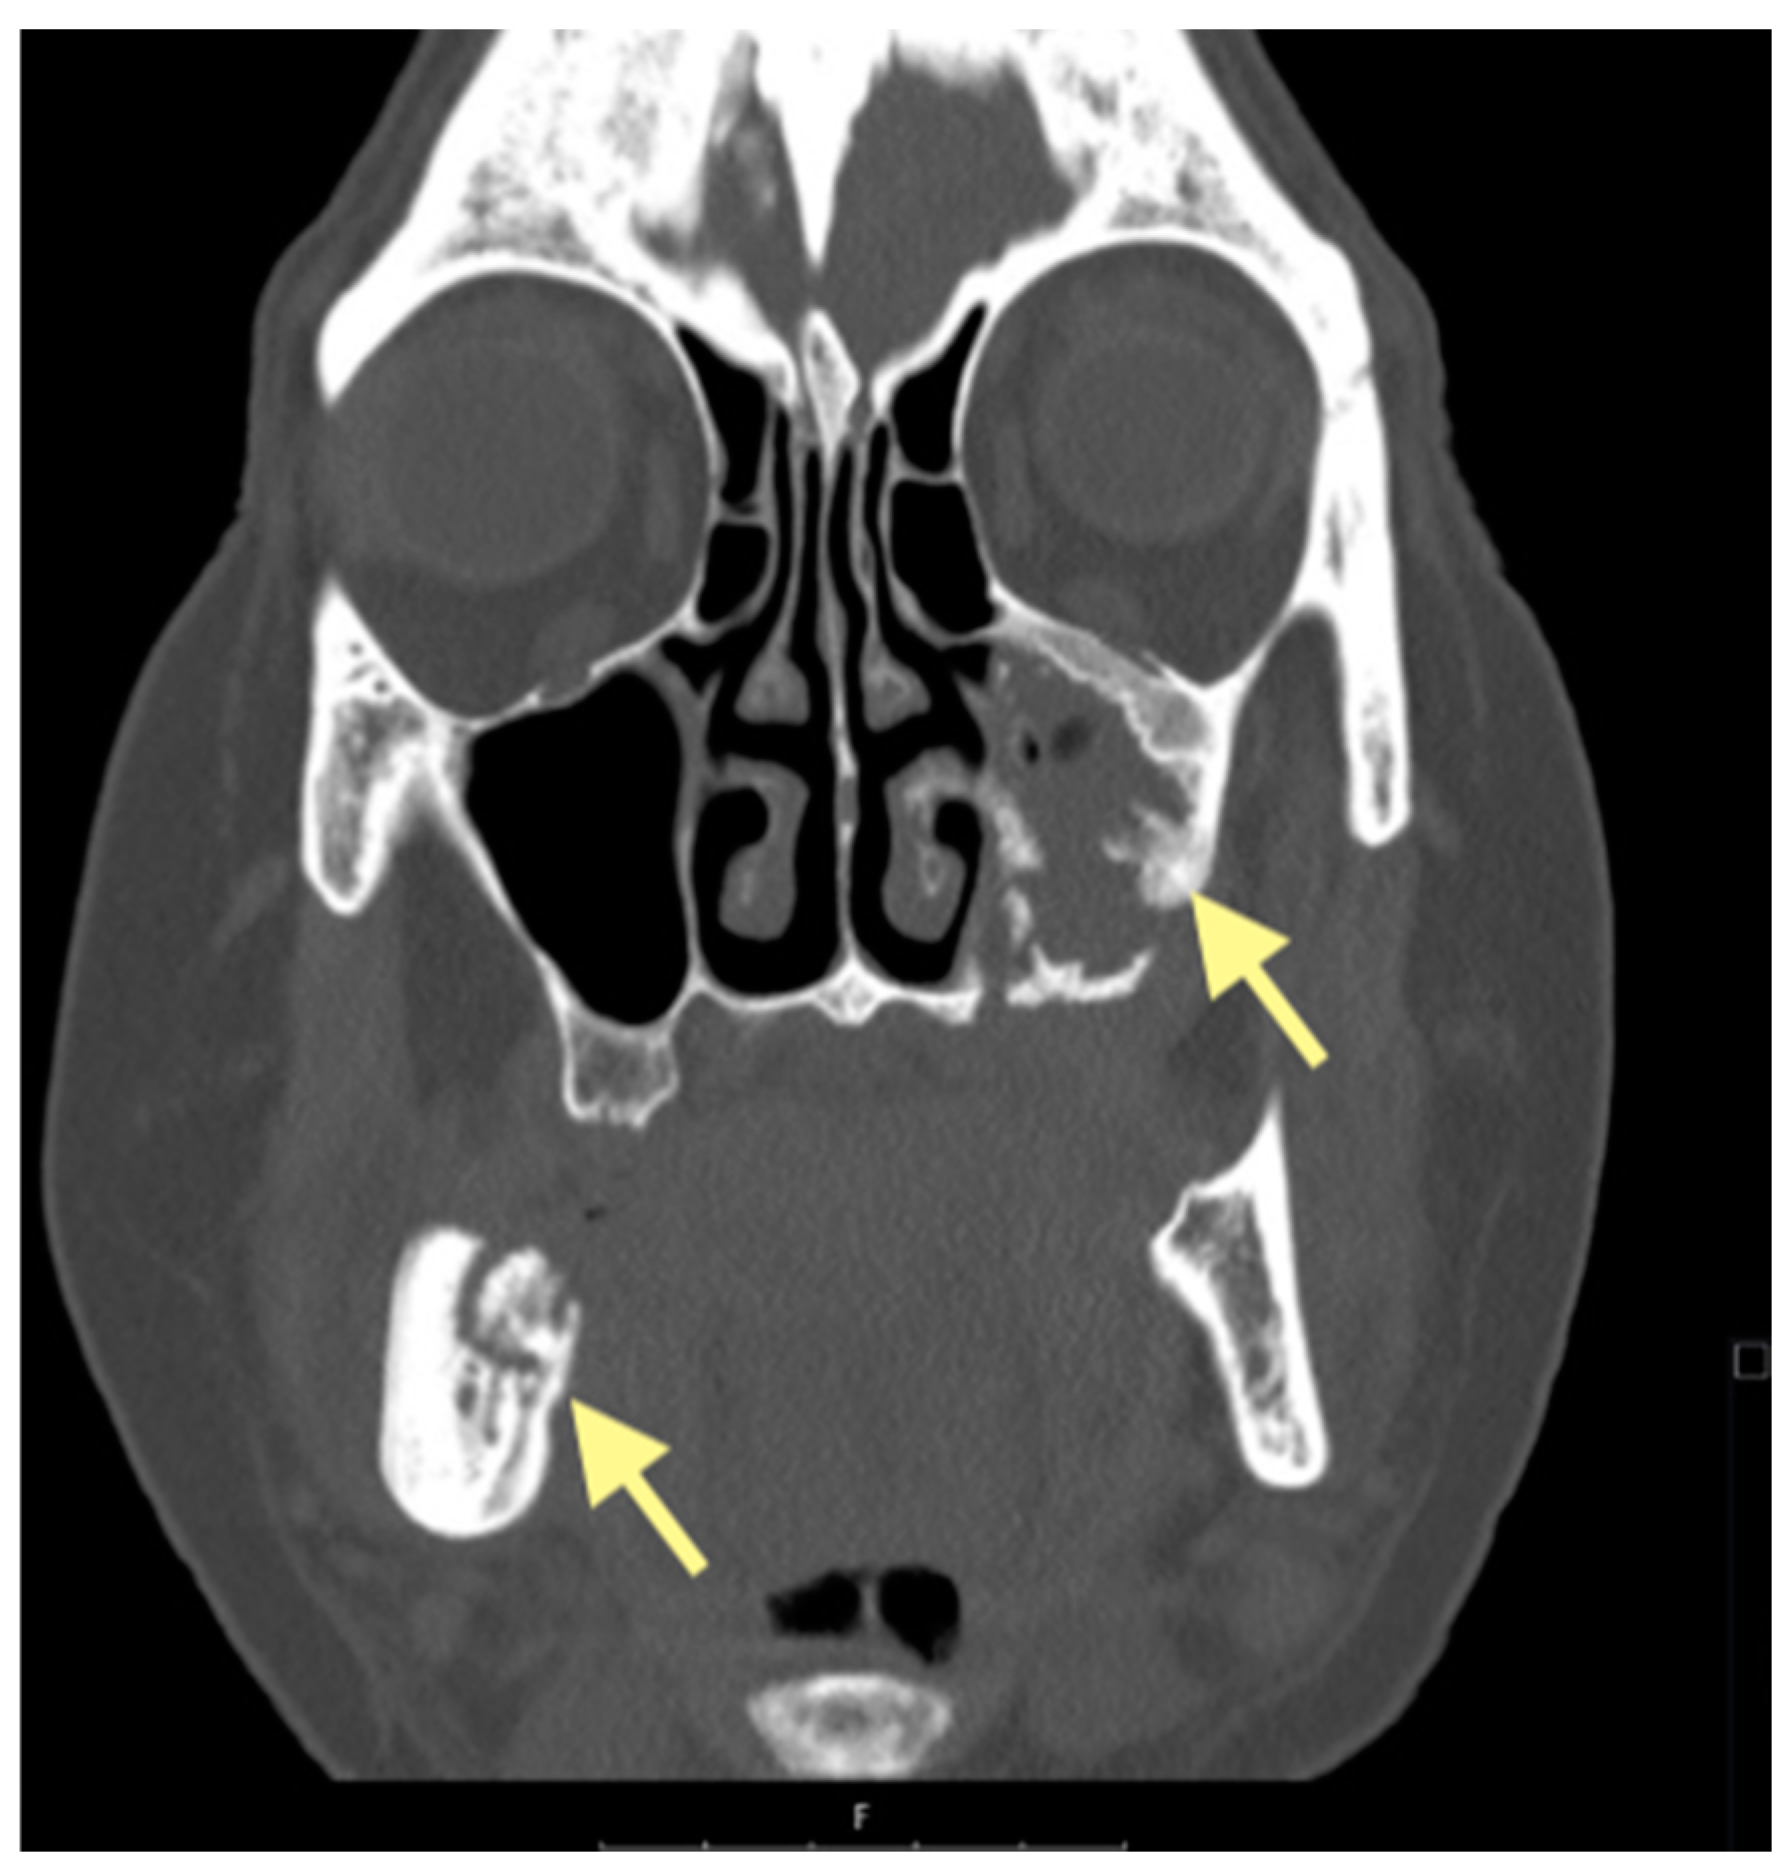

The third patient was a 75-year-old female with osteonecrosis of the mandible and maxilla in the fourth and in the second quadrant (see Figure 7, Figure 8 and Figure 9). The patient had third-stage jaw osteonecrosis. In 2023, the patient was diagnosed with osteonecrosis of the upper and lower jaw caused by antiresorptive therapy (until August 2021, the patient regularly used Zolendronic acid; then, this drug was replaced by the RANKL inhibitor Denosumab). The treatment was periodically complicated by submandibular and submental abscesses. In addition, due to the progression of the underlying disease, constant courses in chemotherapy were administered. The patient underwent three operations, which included sequestrectomy of the jaw with simultaneous use of A-PRF, antrotomy with revision of the maxillary sinus, closure of the oroantral communication, and opening and revision of abscesses of the soft tissues (see Figure 10 and Figure 11)

Figure 9.

CT of the head and facial bones (16 December 2024).